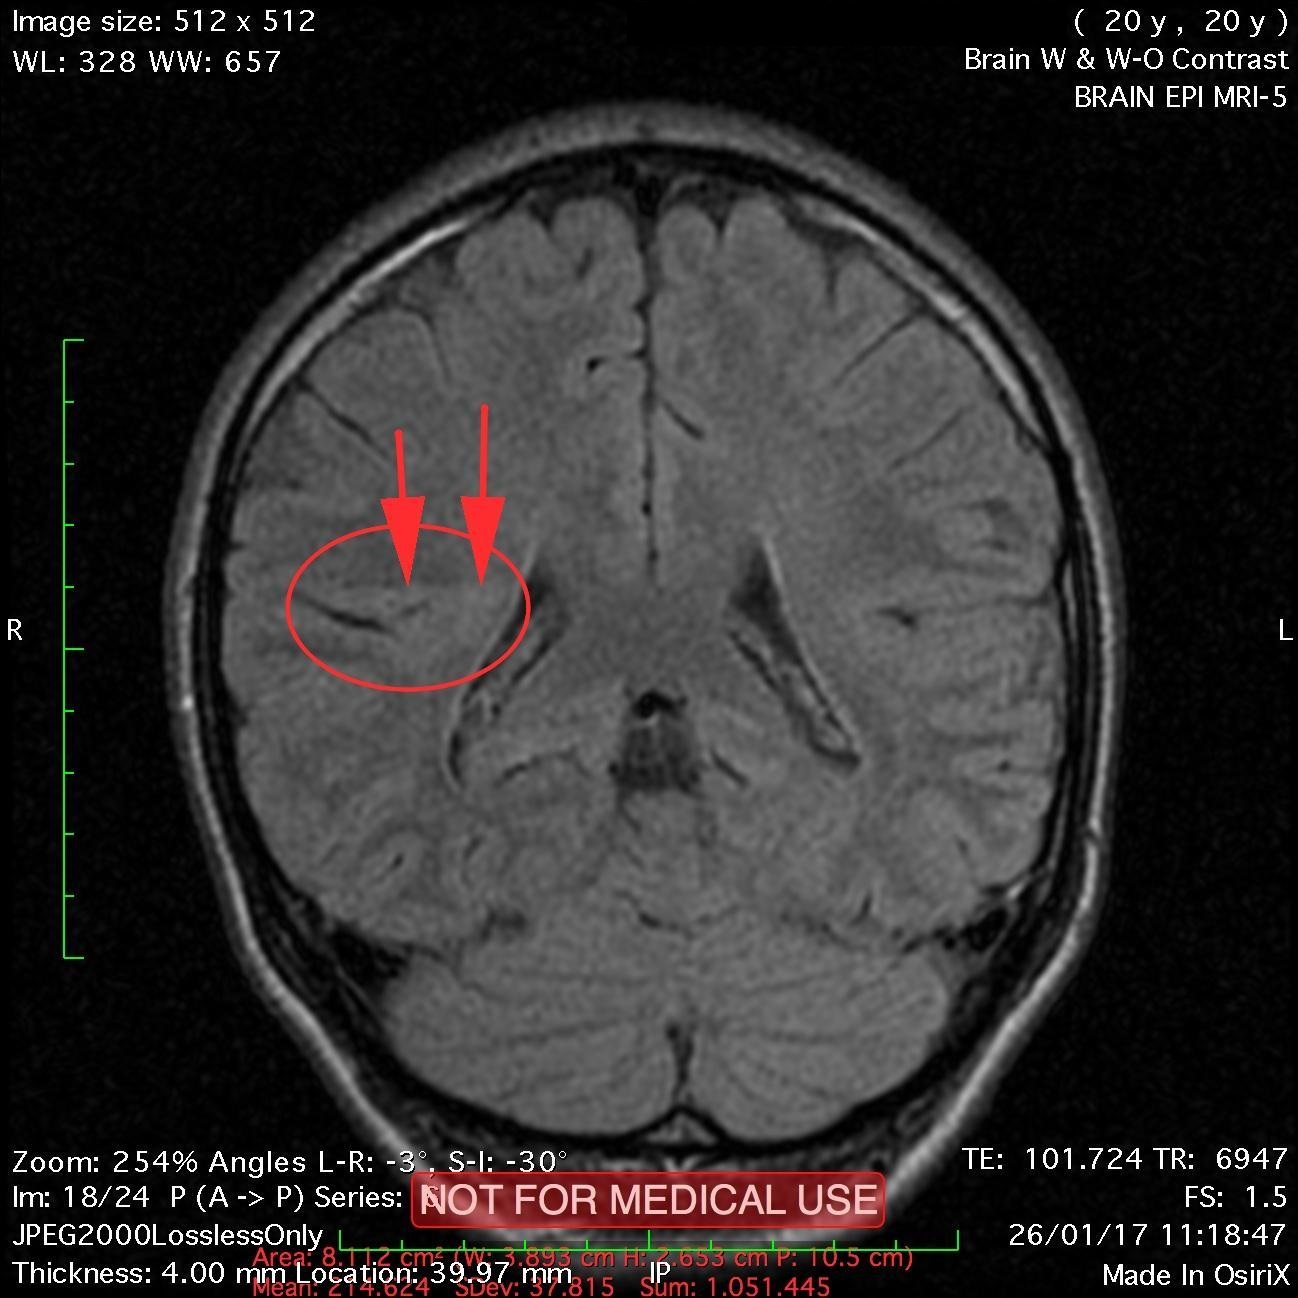

This recent MRI exam WITHOUT Contrast in IHC, revealed a subtle congenital malformation of cortical development within right parietal lobe.

A subtle linear band intensity extending between deep posterosuperior aspect of right Sylvian fissure and posterior aspect of corpus of right lateral ventricle (isointense with gray matter on all sequences). These MRI findings strongly suggest "Type II (Taylor type) focal cortical dysplasia (transmantle cortical dysplasia)" or "transmantle gray matter heterotopia". Virtually, they may be representing two different names for the same entity.

Secondary hippocampal sclerosis is identified, bilaterally (secondary to long-term intractable epilepsy).